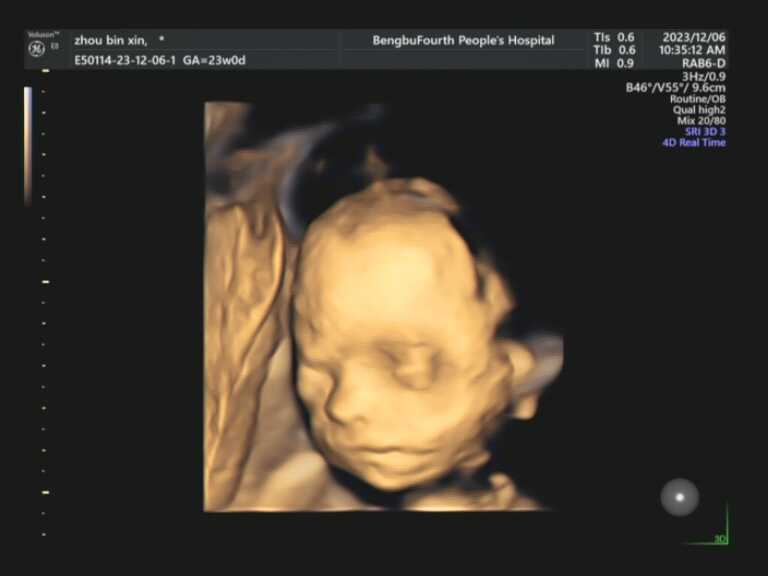

亲爱的准爸准妈,您是否无数次在梦中勾勒宝宝的模样?想象宝宝是像爸爸一样有着高挺的鼻梁,还是像妈妈一样爱笑?现在,您无需再等待十月之久。蚌埠市第四人民医院(市康复医院)高新院区超声科引进超高端美国GE-E8四维彩色超声诊断仪,将为您开启一场奇妙的生命探索之旅。这款被誉为“超声界网红”的设备,是胎儿排畸的顶端配置,搭载全球先进的电子曲面矩阵4D探头,能360°立体清晰展示胎儿各器官发育情况,精准捕捉每一个细节。

在这里,您将看到宝宝在子宫里打哈欠、吮手指、微笑、伸懒腰的可爱瞬间。在这里,您将获得宝宝人生中第一段动态“写真”和“照片”,成为您家庭最珍贵的回忆。

孕22-24周,是做四维彩超的最佳时间段。因为这段时间胎儿的各项器官已经基本发育完全,且羊水较多,更加容易观察胎儿的生长发育状况,孕妈妈们一定要提前预约。